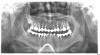

dlz777 Опубликовано 11 сентября, 2010 Поделиться Опубликовано 11 сентября, 2010 Очень ноет зуб пятый или четвертый, справа внизу под мостом. Наверное все-таки пятый где вкладка. Мост стоит уже года 2. Раньше не было таких проблем. Болит уже неделю. Волнами, то накатит то отойдет. Чем полечить? Ссылка на комментарий